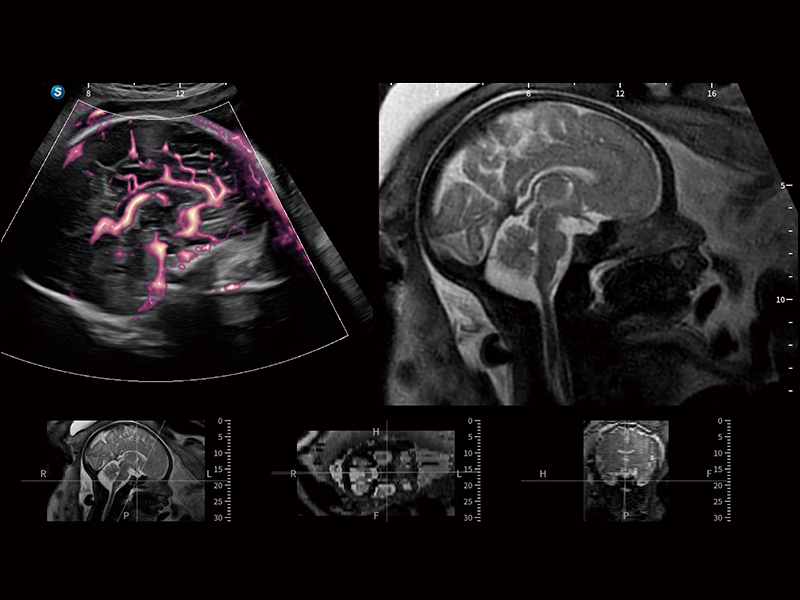

在傳統(tǒng)血流的基礎(chǔ)上優(yōu)化掃查和算法策略,能夠更好的抑制組織信息,提煉紅細(xì)胞運(yùn)動(dòng)信息,得到更高幀頻,高靈敏度和分辨率的血流信號(hào),還原更真實(shí)的血流動(dòng)力學(xué)。

通過光照模型,使二維血流顯示出立體的效果,增加血流的敏感性、成束性,減少外溢??梢院推渌煌难骷夹g(shù)聯(lián)合使用,融合不同技術(shù)的優(yōu)勢(shì)。輕松應(yīng)對(duì)微小血管,增強(qiáng)血流的立體效果,提升視覺敏感性。

通過創(chuàng)新的Matrix E自適應(yīng)濾波算法,能有效濾除軟組織和噪聲信號(hào),最大限度保留超低速微細(xì)血流的信號(hào);結(jié)合超長時(shí)間域算法,極大提升細(xì)微血流的敏感性和空間分辨率,更真實(shí)的反應(yīng)組織、包塊的血流灌注情況。